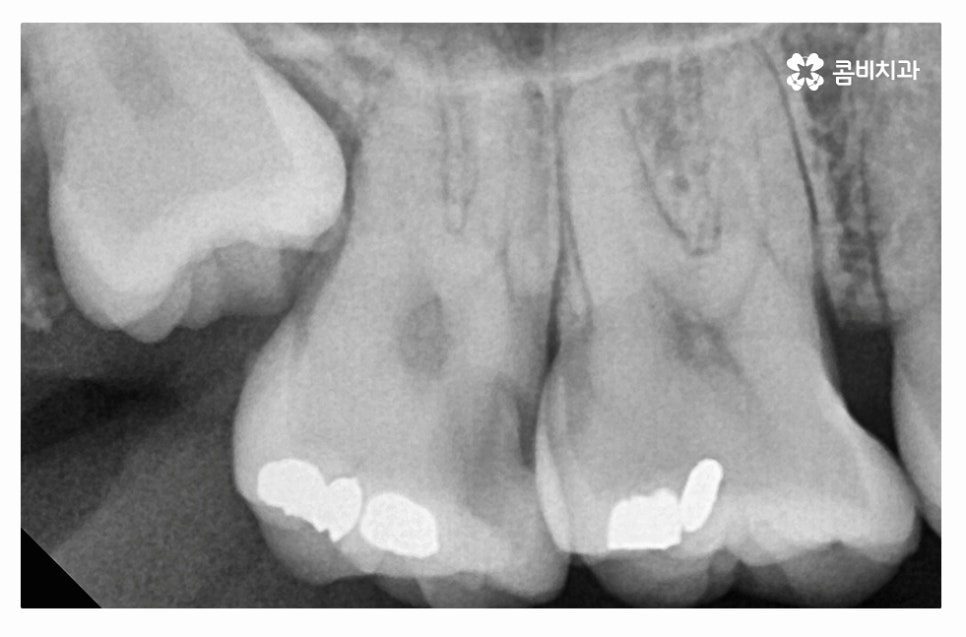

누운사랑니발치 사례를 보면서 설명을 듣는다면 더욱 이해가

잘 되실 텐데 위 사진처럼 사랑니가 어금니 방향으로

자라고 있는 경우에는 치아 사이 충치를 유발하거나

잇몸질환의 원인이 될 수도 있는데요.